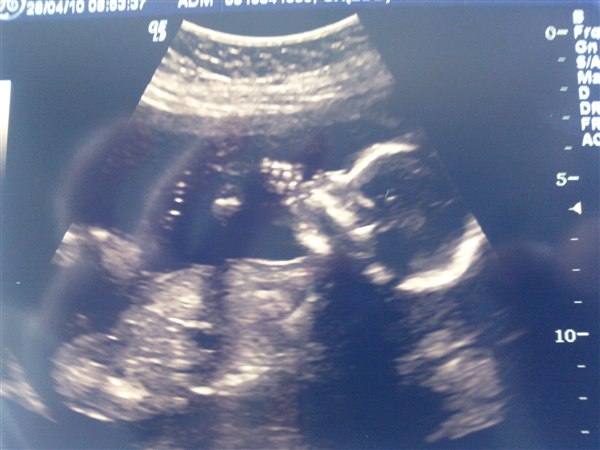

Så kom dagen endelig hvor vi skulle til Md scanning!! Var så nervøs at jeg ikke har fået noget søvn hele natten  Men heldigvis var alt som det skulle være, og vi venter os sørme en lille pige Ville bare lige dele vores glæde med jer..

Så fin hun da er!

Tillykke med datteren og den fine scanning, hehe hun ligner én der liiige skal til at stikke sin hånd i munden

Skønt scanningsbillede, det ligner at hun ligger og synger i en mikrofon